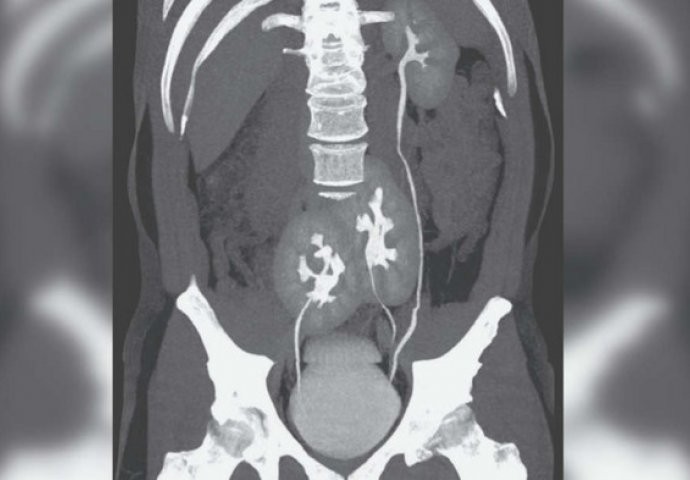

The doctors recommended an X-ray, but what the images showed also surprised them. The scans showed that he had a common problem that they deal with every day, but in addition it was visible that he also had three kidneys. On the left side he had a completely normal kidney, while on the right side there were two kidneys which, according to what could be seen on the scans, were connected to each other.

Unusual arrangement of organs

The ureters were merged into one at the very outlet into the urinary bladder. Many people might assume that this man is lucky because he has three kidneys, but this case is actually very serious. You might think that one kidney could fail during life, as often happens with some people, and therefore the man would have an advantage. According to the doctors, however, that is not the case.